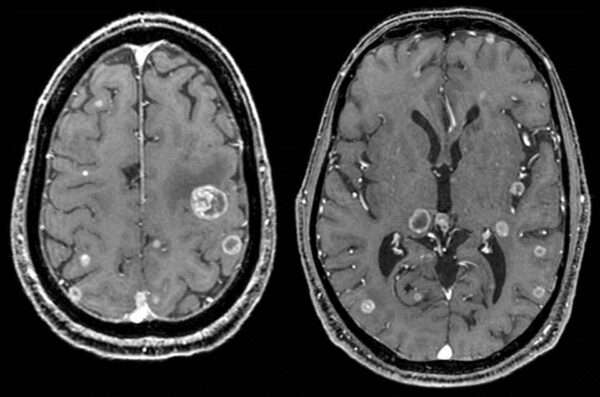

Tumores metastásicos intracraneales

Los tumores metastásicos intracraneales son neoplasias malignas que se originan en sitios fuera del cerebro y se diseminan a través del torrente sanguíneo hasta el sistema nervioso central. Este tipo…